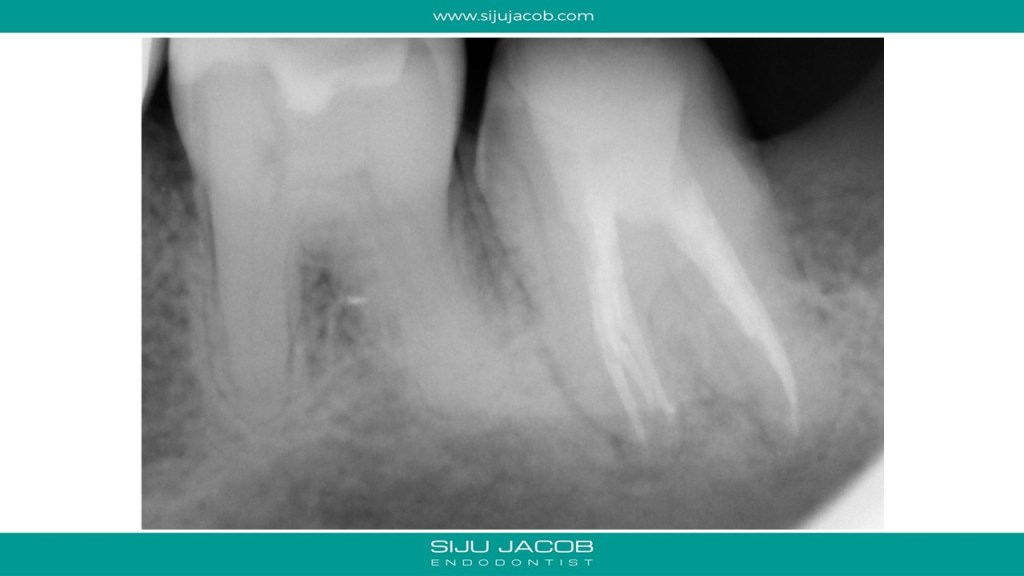

This patient had pain after endo and crown on a mandibular second molar. She went back to the practitioner who removed the crown and removed the old gutta percha. The tooth subsequently flared up and she landed in my office. I found a missed middle mesial. We put the tooth on long-term calcium hydroxide intra canal medication, extracted the wisdom tooth and waited for the tenderness to subside before obturation . Pictures are self-explanatory